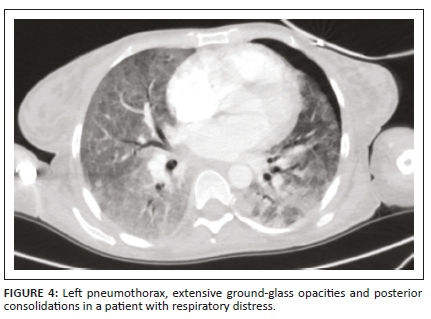

A complete list of the incidental findings on CTPA is summarised in Table 3 and the pulmonary findings in PE-negative cases are illustrated in Figure 2. The most common parenchymal findings in PE-negative cases were as follows: solid pulmonary nodules (52.5%), non-wedge-shaped consolidation (45%) (Figure 2a, b, c), emphysematous changes (17.5%) (Figure 2d) and lung cavities (10%) (Figure 2e, 2f). Pleural effusion was also found in 17% of PE-negative studies (Figure 3). One of the patients in the study had a pneumothorax (Figure 4). The most common incidental cardiac finding was cardiomegaly (52.5%). Various examples of extra-pulmonary incidental findings are demonstrated in Figure 5, including a case of extensive pneumobilia (Figure 5b) and a patient found to have multiple rib fractures (Figure 5c). The most common other intra-thoracic finding in PE-negative cases was enlarged mediastinal or hilar lymph nodes without significant mass effect (52.5%), whilst 7.5% had reported an oesophageal abnormality (Figure 5a); the most common extra-thoracic finding was hiatus hernia (7.5%).